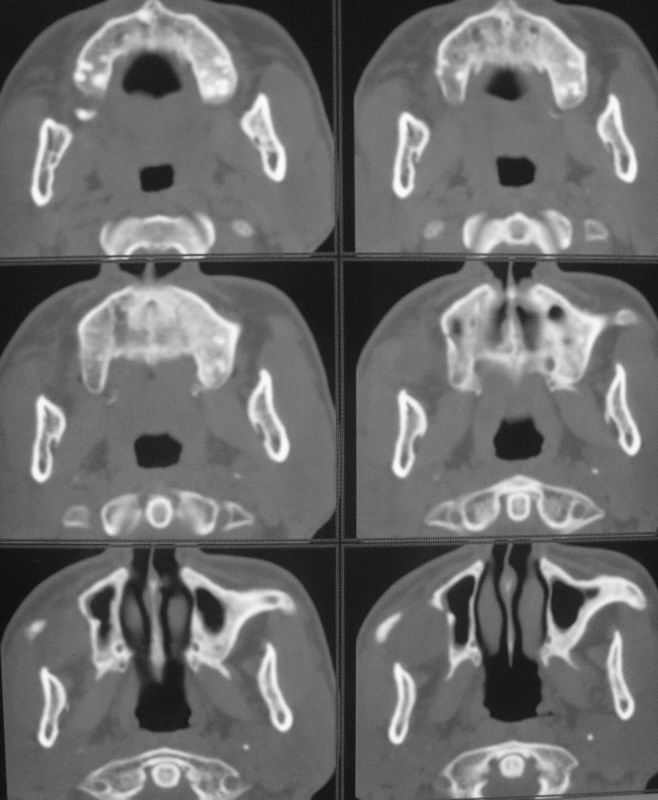

以下是引用zsl6918在2008-5-6 14:41:00的发言:[br]右侧颞下窝内囊性占位(增强未见强化),同侧上颌窦受压变形移位,提示慢性过程。右侧上颌骨局限性吸收破坏,提示良性病变。

以下是引用xuhuihong在2008-5-6 14:57:00的发言:[br]右侧颞下窝内囊性占位(增强未见强化),同侧上颌窦受压变形移位骨质吸收变薄,提示慢性过程。右侧上颌骨局限性吸收破坏,提示良性病变。考虑神经源性肿瘤可能,期待结果。